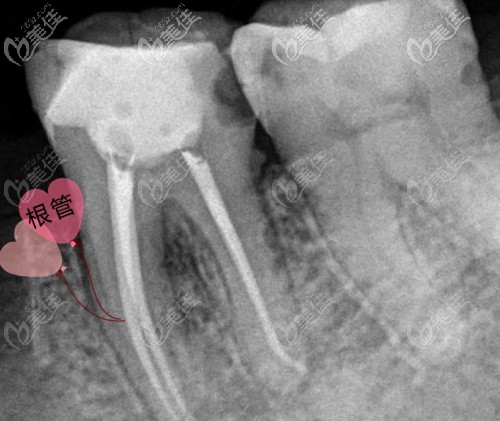

前牙相對(duì)而言根管系統(tǒng)簡單一些,一般只有一個(gè)根管(牙神經(jīng)管),而后牙根管系統(tǒng)就復(fù)雜多了,有3個(gè)、4個(gè)或者5個(gè),而且后牙的根管也比較細(xì)小,更加不易治療。那收費(fèi)自然也就比前牙貴了。

大致來說,一顆牙根管再治療的費(fèi)用在1000元~1800元左右。與存在殘髓、遺漏根管或根充不完善等有關(guān)。建議在有顯微鏡的牙科治療,以確保療效。